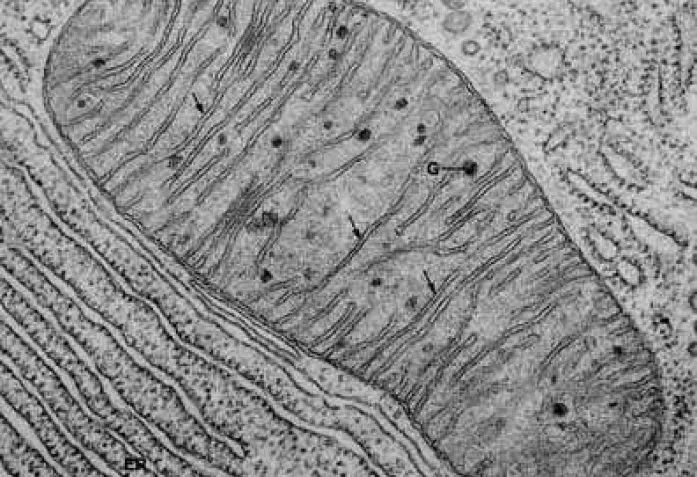

Митохондрии - энергетические "станции" клетки

Дефекты окисления жирных кислот – болезнь, от которой страдает один новорожденный ребенок из трех тысяч. Подобные расстройства могут привести к повреждению мышечных тканей, в том числе, сердечной, если больной не соблюдает строжайшую диету в течение всей жизни. Как другие тяжелые нарушения обмена веществ – диабет второго типа и ожирение, - дефекты окисления жирных кислот связаны с дисфункцией митохондрий в клетках. Напомним, именно в митохондриях молекулы, полученные организмом с пищей, превращаются в энергию, используемую клеткой для жизнедеятельности.

Однако один из главных потребителей этой молекулы – фермент PARP1. Исследования показали, что, сокращая количество последнего, например, с помощью медикаментов Paribs, можно добиться увеличения количества свободных молекул NAD+, и, соответственно, – белка SIRT1. Действительно, у крыс с недостатком фермента PARP1 наблюдается активация белка SIRT1: митохондрии функционирует гораздо лучше, сжигают жирные кислоты, не прибегая к использованию глюкозы. Результат: защита от нарушений обмена веществ у этих животных гораздо более эффективна.